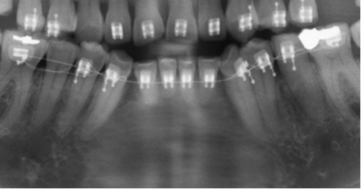

Los resultados mostraron que en el 48 % de la población se encontró algún hallazgo relacionado con la pulpa dental, con frecuencias similares entre hombres y mujeres, siendo el tratamiento endodóntico el más frecuentemente encontrado (Tabla 1, Fig. 1). El rango del número de endodoncias por radiografía fue de 1 a 18. El 86,4 % de las radiografías presentaron de 1-5 endodoncias, 11,4 % de 6-10 y el 2,2 % de 11-18. La presencia de zona radiolúcida periapical seguida por la reabsorción (Fig. 2), fueron los siguientes hallazgos más frecuentes. (Tabla 1)

El análisis de la presencia de zona radiolúcida periapical, mostró que del total de dientes en boca, el 0,6 % de los que no tenían endodoncia tienen lesiones apicales mientras que el 11% de los que tienen endodoncia se asocian con una lesión apical (p<0,000000). Sin embargo el cálculo del OR (OR=0,047) mostró una relación negativa de riesgo entre tener una endodoncia y presentar lesión apical. De los 389 dientes en los que se observó el hallazgo compatible con radiolucidez periapical, 171 (44 %) tenían tratamiento endodóntico, de los cuales 66 % estaban subobturados, 31% bien obturados y 3% sobreobturados.